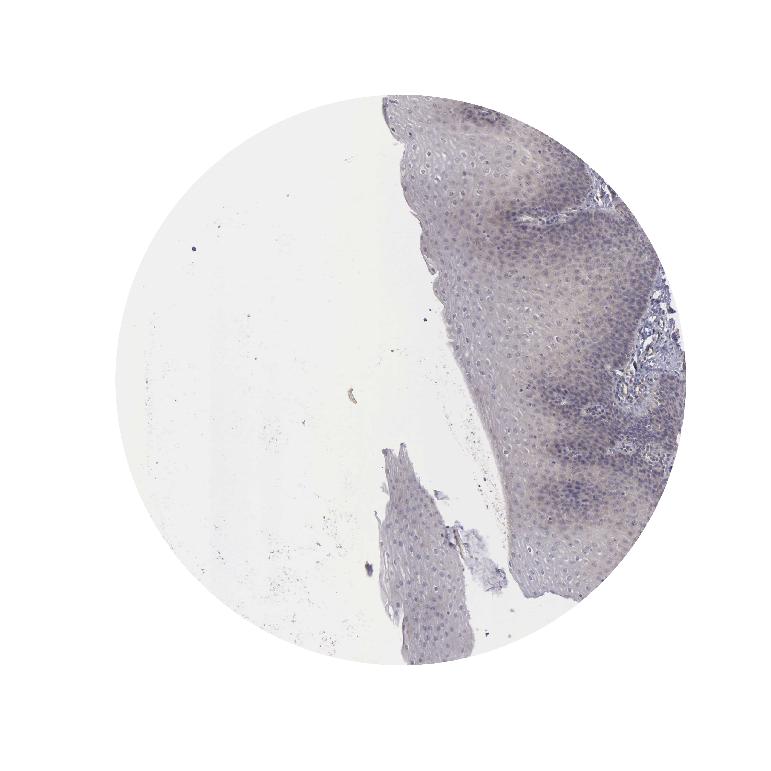

ESOPHAGUS - Antibody stainingi

Antibody staining in the annotated cell types in the current human tissue is reported as not detected, low, medium, or high, based on conventional immunohistochemistry profiling in selected tissues. This score is based on the combination of the staining intensity and fraction of stained cells.

Each image is clickable and will lead to virtual microscopy that enables deeper exploration of all samples and also displays staining intensity scores, fraction scores and subcellular localization as well as patient and tissue information for each sample.

Antibody HPA000721Antibody HPA001419

Squamous epithelial cells Not detectedLow